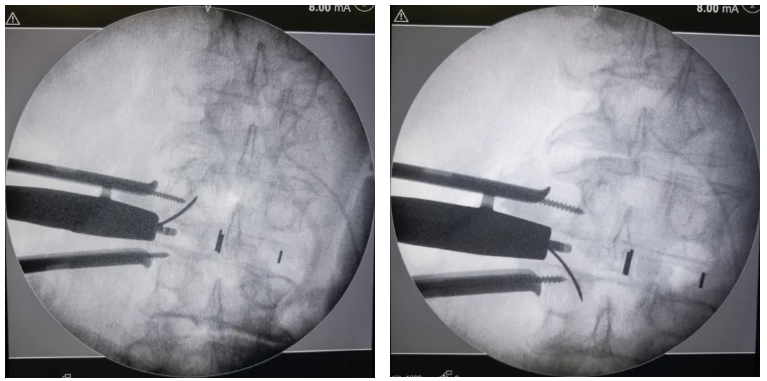

術中(zhong)影(ying)像

通道建立及椎間減(jian)壓(ya)——

試模確認(ren)融合器(qi)規格——

植入融合器(qi)——

透(tou)視確(que)認融合器位(wei)置及尺寸——